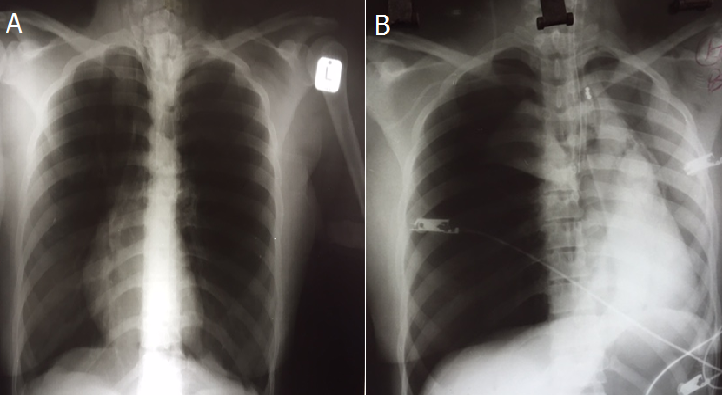

Status asthmaticus with pseudo-dextrocardia, complicated by iatrogenic tension pneumothorax

A 25-year old female, with a background of asthma, presented with acute shortness of breath. On examination the patient was in severe respiratory distress with expiratory wheezes. She was nebulized with ipratropium and fenoterol. A chest x-ray revealed pseudo-dextrocardia and air trapping (A). She did not respond to inhaled bronchodilator therapy. Intravenous hydrocortisone and magnesium sulphate were administered. The patient deteriorated and was subsequently ventilated and intravenous aminophylline initiated. After intubation and ventilation, a central venous line was inserted. The patient deteriorated immediately after central line placement and an arterial blood gas showed type 2 respiratory failure with respiratory acidosis. The repeat x-ray revealed a right sided tension pneumothorax with displacement of the mediastinum to the left, incorrect placement of the central line, endotracheal tube and nasogastric tube (B). The central line and nasogastric tube were removed and an intercostal drain was inserted. The endotracheal tube was adjusted. The pneumothorax resolved and the patient made an uneventful recovery. The patient was mechanically ventilated, had severe airway obstruction with air retention and had central venous line insertion, all of which are risk factors for development of tension pneumothorax Tension pneumothroax requires immediate intercostal chest drain insertion.